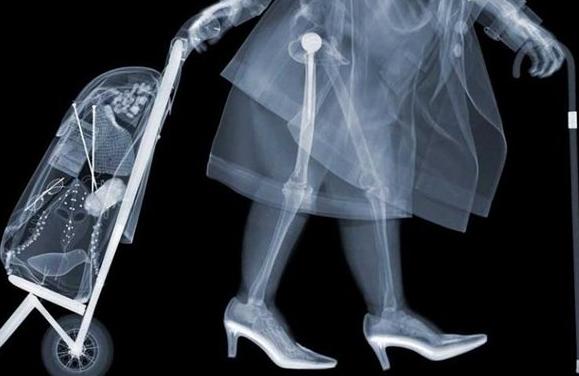

X射线-----相当于把蛋糕压扁检查

原理:X光穿过人体,不同部位吸收射线,底片上不会曝光或部分曝光,洗片后这个部位就是白色的。

优点:快捷、价廉。

缺点:受制于深浅策划的影像互相重叠和隐藏,有时需要多次多角度拍摄X光片才能看清。

X射线是著名的伦琴发现的,它是影响医学的开端。X线发明的故事大家也都熟悉,伦琴在一个偶尔的机会下从X射线现中看见了自己手的骨骼。所以说X射线主要是用来看骨头。

此外还有一个最常见的作用是拍胸片,主要是粗略的看一下肺部和心脏的轮廓。一些诸如肺部感染,先天性心脏病导致心脏的大小形态变化,还有肺癌之类的典型的影像表现还是可以一目了然。还有人问什么透视和拍片有什么区别。简单的说透视就是医生在X光下看一眼,拍片就是把片子打印出来。